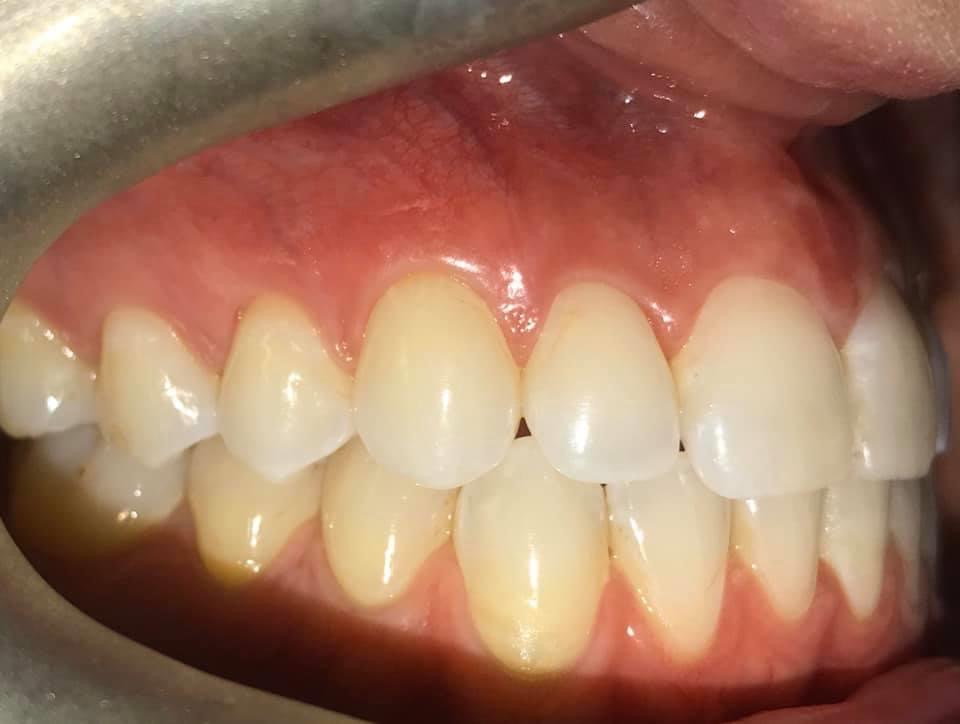

BEFORE AND AFTER PICTURES: